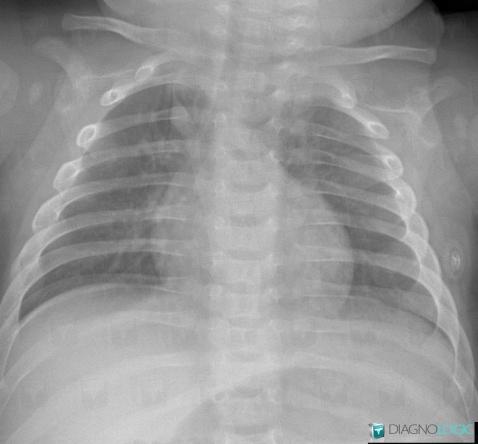

Scissure azygos, Veines - Thorax, Radio

Voici les informations spécifiques à l'image clé ci dessus:

- Diagnostic Scissure azygos, Localisation(s) Veines - Thorax, comportant les gammes